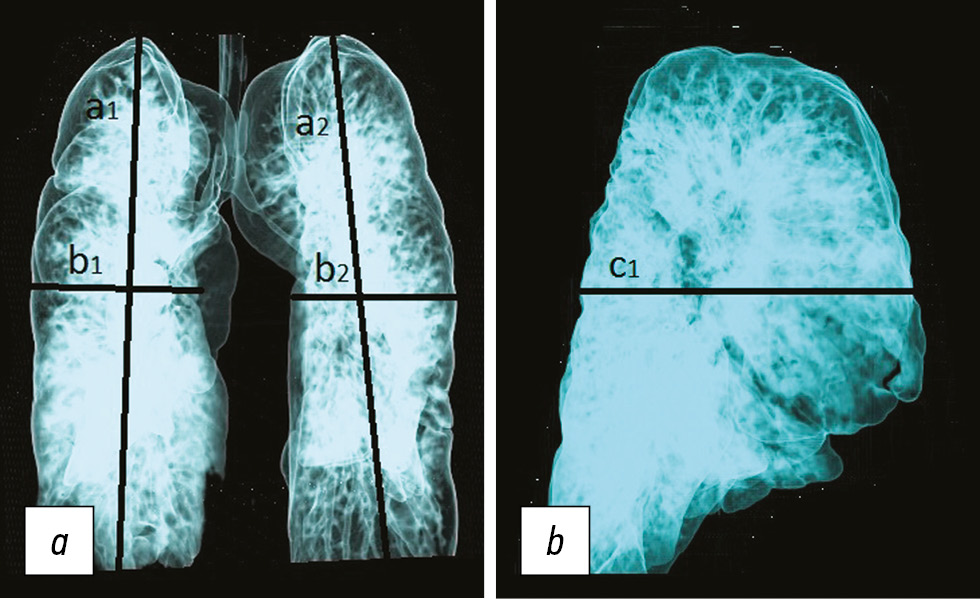

При расчете объема легочной ткани с помощью программы RadiAnt DICOM Viewer 2020.1 в режиме 3D-MVR (трехмерная мультиобъемная реконструкция) объем правого легкого составил 617,3 см3, левого 601,9 см3 (рис. 2) (условно принимая форму легкого за параллелепипед, объем каждого легкого определяли путем перемножения показателей а×b×с, где вертикальный размер (а) оценен как максимальное вертикальное расстояние от верхушки до основания легкого (а); поперечный (b) и переднезадний (с) размеры измеряли на уровне максимальной деформации грудино-реберного комплекса (ГРК).

Рис. 2. Параметры расчета условного объема легких при трехмерной мультиобъемной реконструкции (3D-MVR) легких: а — в переднезадней проекции; b — в боковой проекции. a, b, c — показатели объема легких, индексы 1 и 2 обозначают правое и левое легкое соответственно

Fig. 2. Calculation of an arbitrary lung volume: a — 3D-MVR in the front-rear projection of the lungs; b — 3D-MVR in lateral projection of the lungs (See the text for the details)